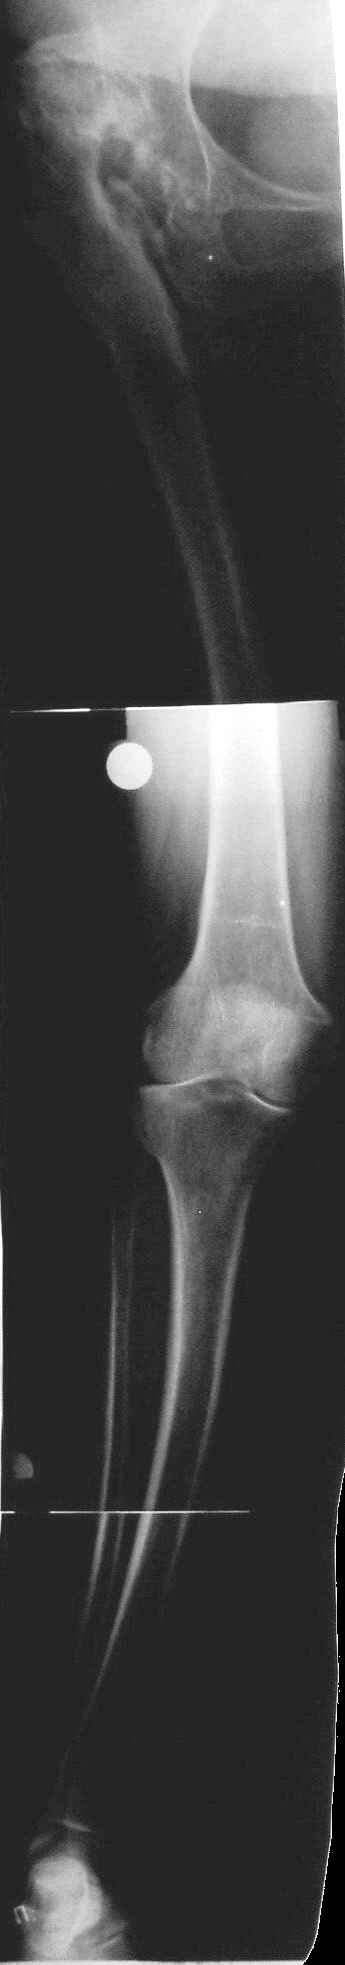

Пациентка 1953 г.р. поступила в клинику с диагнозом: "Деформирующий артроз в неоартрозе III ст. между головкой правого бедра и правой подвздошной костью, исход открытого вправления врождённого вывиха правого бедра. АВНГБ слева III-IV ст., коксартроз слева IIIст.

Из анамнеза: в возрасте 14 лет - открытое вправление врождённого вывиха правого бедра. В 1980 г. остеотомия, дистракционный остеосинтез правой бедренной кости.

Пациентка поступила для эндопротезирования правого тазобедренного сустава. Учитывая наличие вальгусной деформации правого бедра и костей правой голени, возник вопрос, что выполнять в первую очередь - эндопротезирование, или же корригирующие остеотомии с исправлением оси конечности? Мнения коллег разделились.